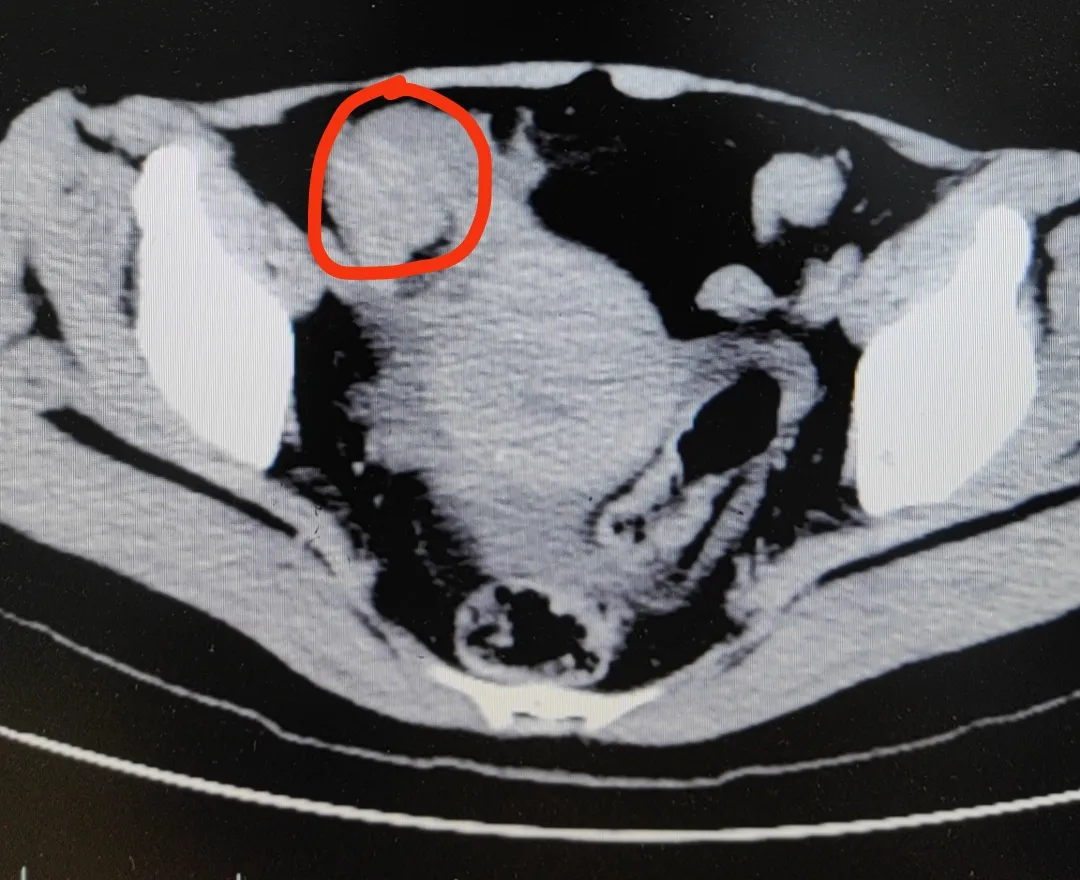

近日,患者冯女士(化名)在家一口气连吃3只柿子,晚餐又吃了2只大闸蟹。结果当天晚上,冯女士突然开始肚子痛,疼得全身冒冷汗,还不停呕吐。忍了两天后,冯女士终于忍无可忍,来到了医院。

医生高度怀疑,冯女士发生了绞窄性肠梗阻。最后手术从肠子里切出一堆“石头”,也就是俗称的“柿石症”,最大的直径有4公分!